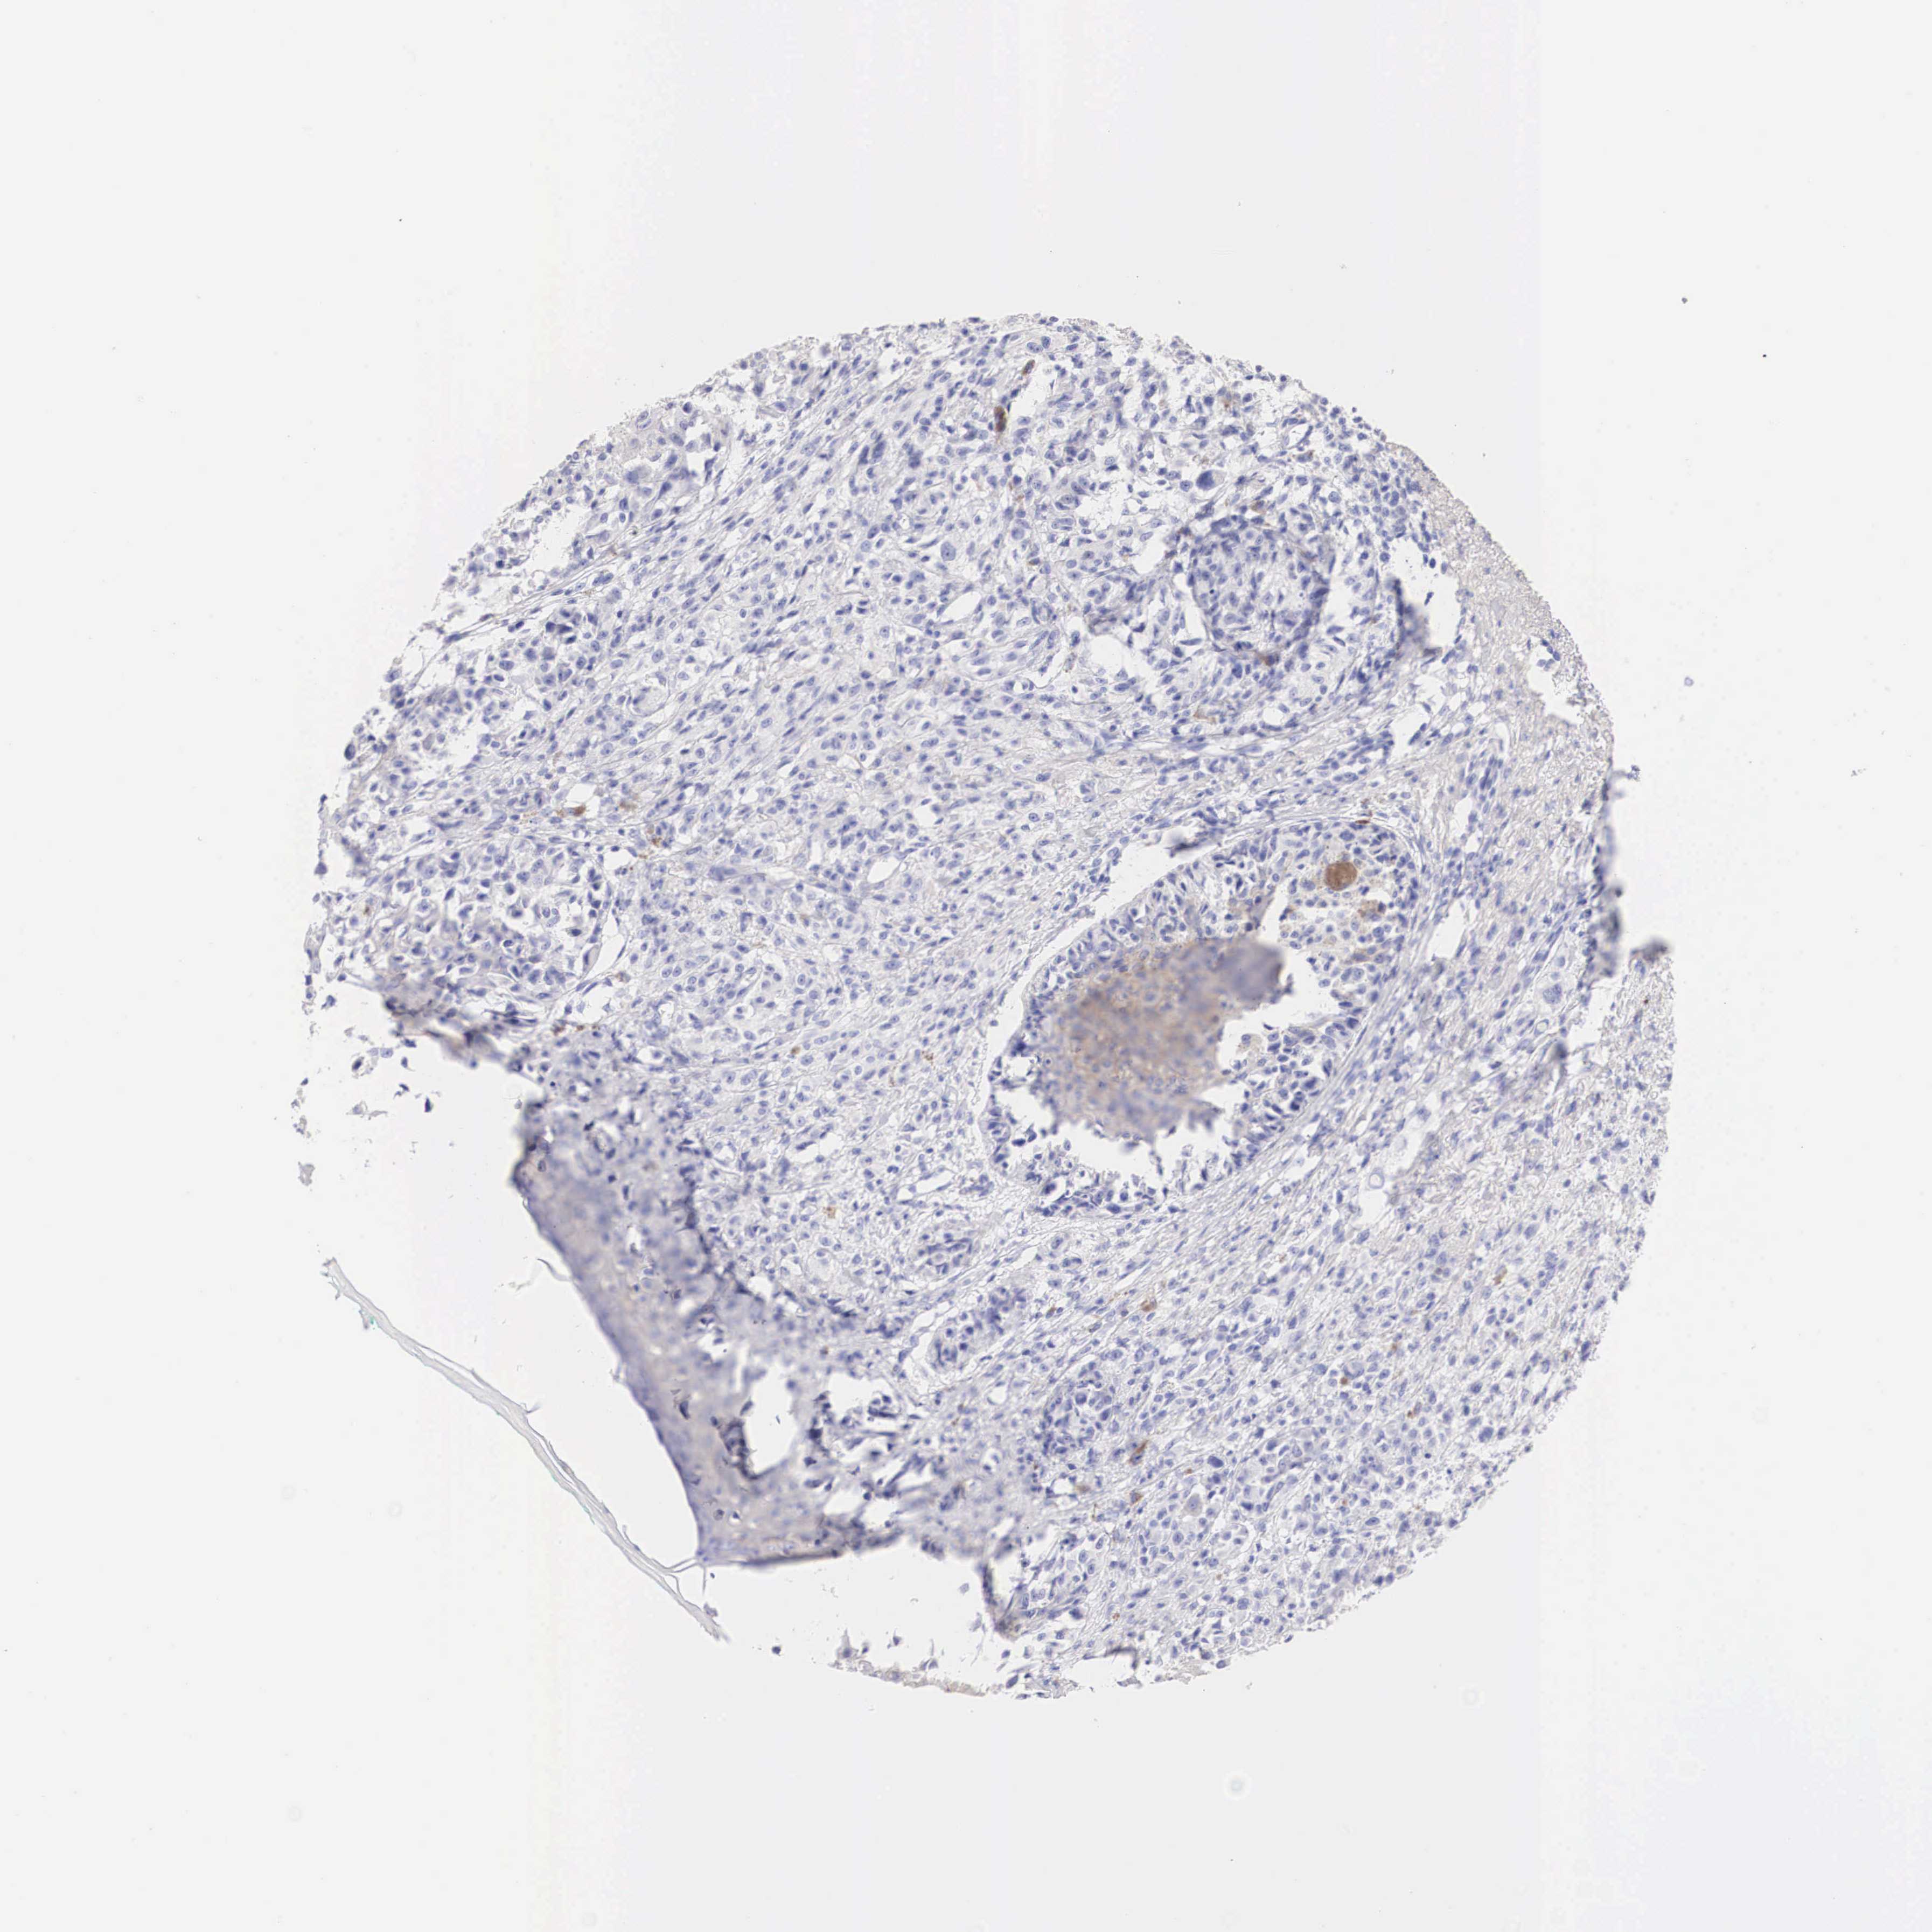

MELANOMA - Protein expressioni

A mouse-over function shows sample information and annotation data. Click on an image to view it in a full screen mode. Samples can be filtered based on level of antibody staining by selecting one or several of the following categories: high, medium, low and not detected. The assay and annotation is described here.

Note that samples used for immunohistochemistry by the Human Protein Atlas do not correspond to samples in the TCGA dataset.

Antibody stainingi

Antibody staining in the annotated cell types in the current human tissue is reported as not detected, low, medium, or high, based on conventional immunohistochemistry profiling in selected tissues. This score is based on the combination of the staining intensity and fraction of stained cells.

Each image is clickable and will lead to virtual microscopy that enables deeper exploration of all samples and also displays staining intensity scores, fraction scores and subcellular localization as well as patient and tissue information for each sample.

Antibody HPA001383

Antibody CAB000043

Antibody CAB020416

Antibody CAB062555

Staining

High

Medium

Low

Not detected

Intensity

Strong

Moderate

Weak

Negative

Quantity

>75%

75%-25%

<25%

None

Location

Nuclear

Cytoplasmic/membranous

Cytoplasmic/membranous,nuclear

Malignant melanoma, NOS

Malignant melanoma, Metastatic site